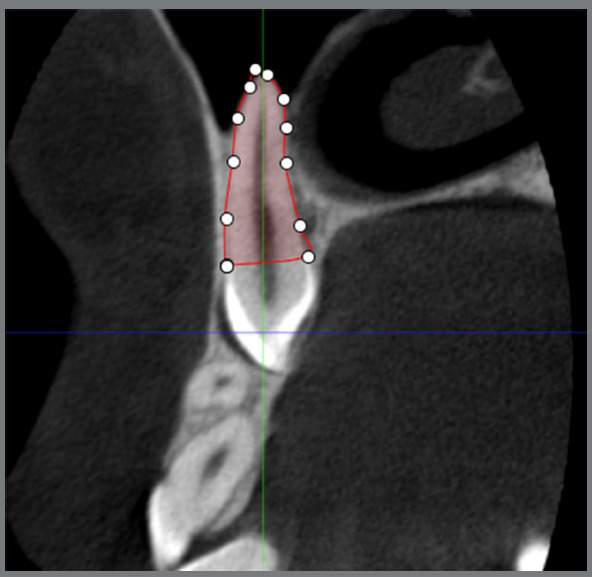

Methods: This cross-sectional study was performed on cone-beam computed tomography (CBCT) scans of 100 patients (49 females and 51 males) with unilateral maxillary canine impaction. The images were loaded in Planmeca Romexis Viewer, and root layers between the cementoenamel junction and apex were reconstructed at 600-µm intervals. At each layer, the root boundary was marked, and finally, the root volume was calculated by multiplying the layers' area by the thickness of 600 µm. The root size of canines and lateral incisors was compared between the impaction and normal eruption sides.

Abstract Image